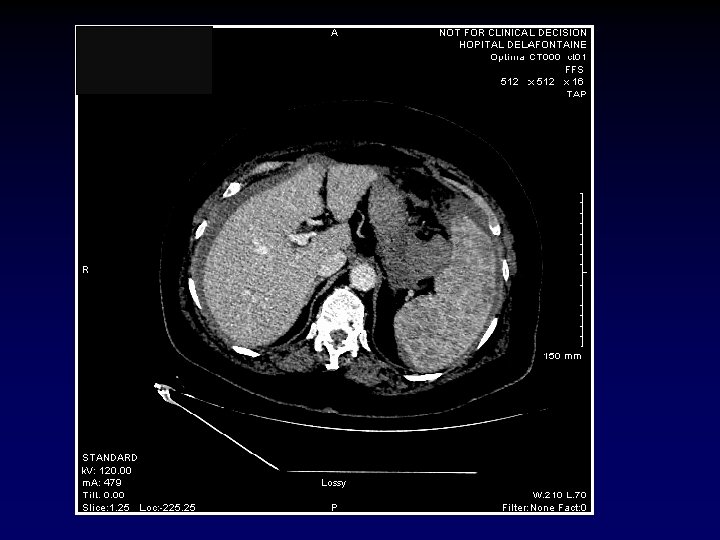

SCANNER ABDOMINAL AVEC IV le 07/01 Hématome avec aspect de fuite active au bord supéro-interne de la rate avec majoration de l’épanchement péritonéal et aspect de fuite active de contraste à deux niveaux Densité splénique hétérogène au temps portal prenant un aspect nodulaire